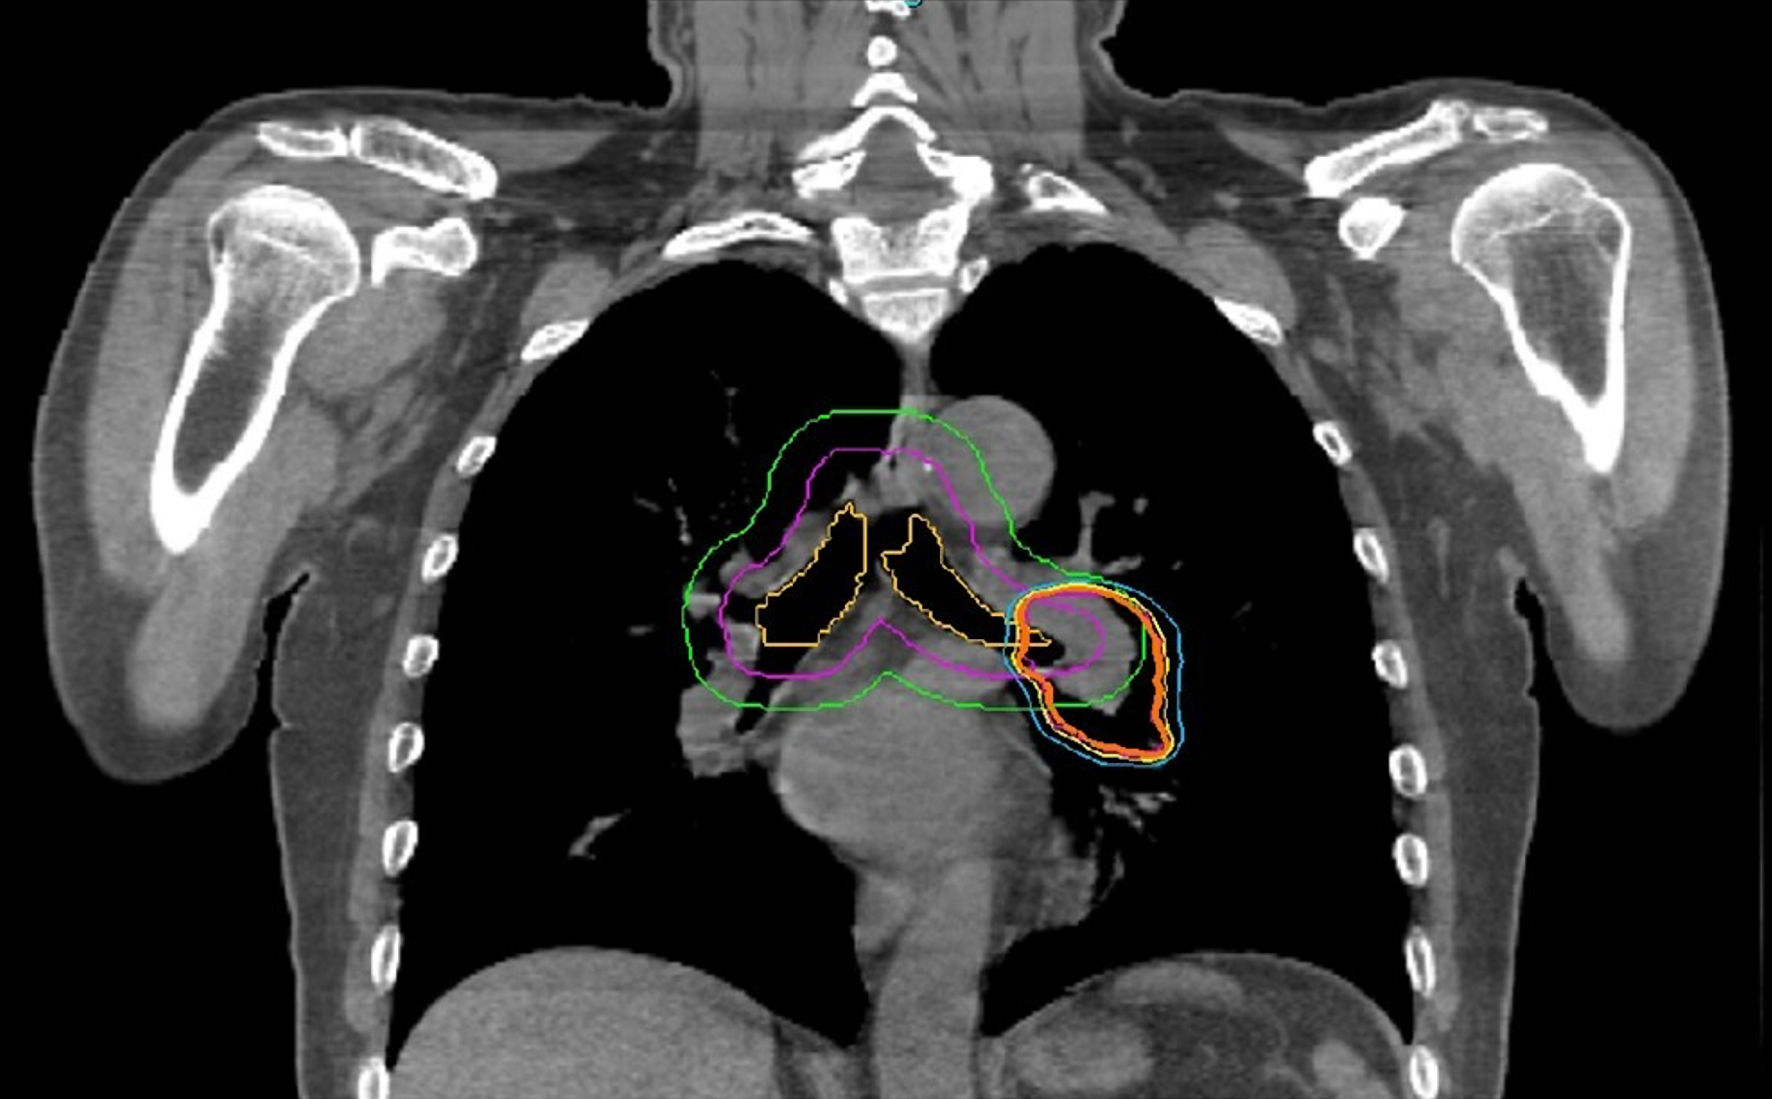

SBRT was applied to the primary tumor in 22 cases, to one LN metastasis each in five cases, to one metastasis each in five cases, to a total of seven metastases in two cases, and to the primary tumor and two LN metastases in one case. In addition to seven centrally located LN lesions, one primary lung lesion was also centrally located and received 52.5 Gy/7 fx, and local recurrence was not seen at follow-up (Fig. 1). Two-view, one-view, and zero-view tracking were applied to 12% (n = 5), 31% (n = 13), and 57% (n = 24) for all lesions, and 15% (n = 5), 38% (n = 13), and 47% (n = 16) for peripheral lesions, respectively (Table 2). The median prescription dose for all lesions was 48 Gy/4 fx (28 - 55 Gy/1 - 7 fx). The median biological effective dose (BED10) was 105.6 Gy (48 - 151.2). The median beam on time (BOT) was 25 min (12 - 42 min). The median duration of treatment was 7 days (1 - 14 days). OAR tolerance doses were not exceeded in any of the cases. The percentage difference of measured and calculated dose was < ± 5% for all treatment plans.

![]() Click for large image | Figure 1. Organ at risk and isodose distribution in a case with centrally located primary lung lesion |